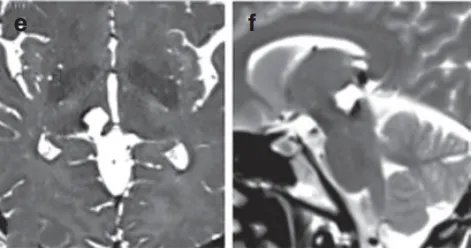

就像术前拍的超清晰的“脑部写真”一样,术后的轴向(e)和矢状T2wMRI(f)的图片,清清楚楚地展示了医生的高超手艺。那颗血管瘤真的不见了,证实已被完整切除。

术后MRI影像

而患者呢?她不仅没有出现任何额外的神经功能缺损,反而在短短10天后便出院,恢复良好(h)!这台手术的主刀正是国际神外大咖巴特朗菲教授。